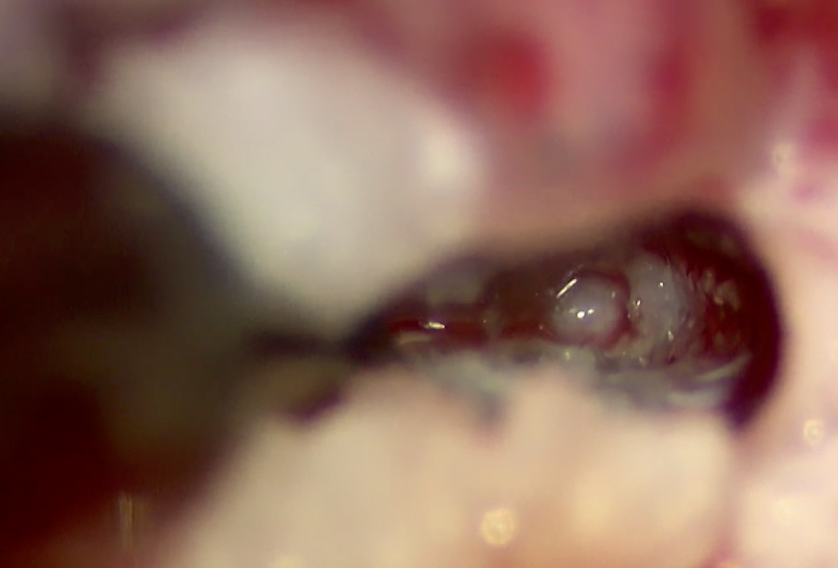

椎間板物質を鉗子で摘出しているところです。

椎間板物質が摘出され、一番奥に神経が見えています。

椎間板物質をすべて摘出すると神経が見えてきます。押されている様子などがなければ終了として閉創して終了となります。